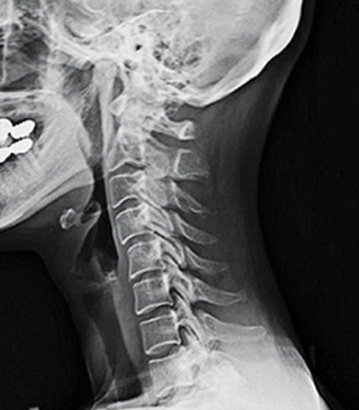

앞서 언급한 바와 같이 목의 자연적인 전만증은 경추를 안쪽으로 C자 모양으로 굽게 하는데, 그 곡률 정도가 20~40도 범위에 속하면 정상적이고 건강한 경추 전만증의 범위로 볼 수 있습니다. 만약 사람이 경추 전만증의 상실을 경험하고 그 정상 범위에 속하지 않는다면 이는 목이 지나치게 곧게 되었다는 것을 의미합니다.

경추 전만증의 상실은 목이 지나치게 곧게 되었다는 것을 의미하며, 이는 앞으로 머리 자세 및 군사 목과 같은 여러 가지 문제를 일으킬 수 있습니다.